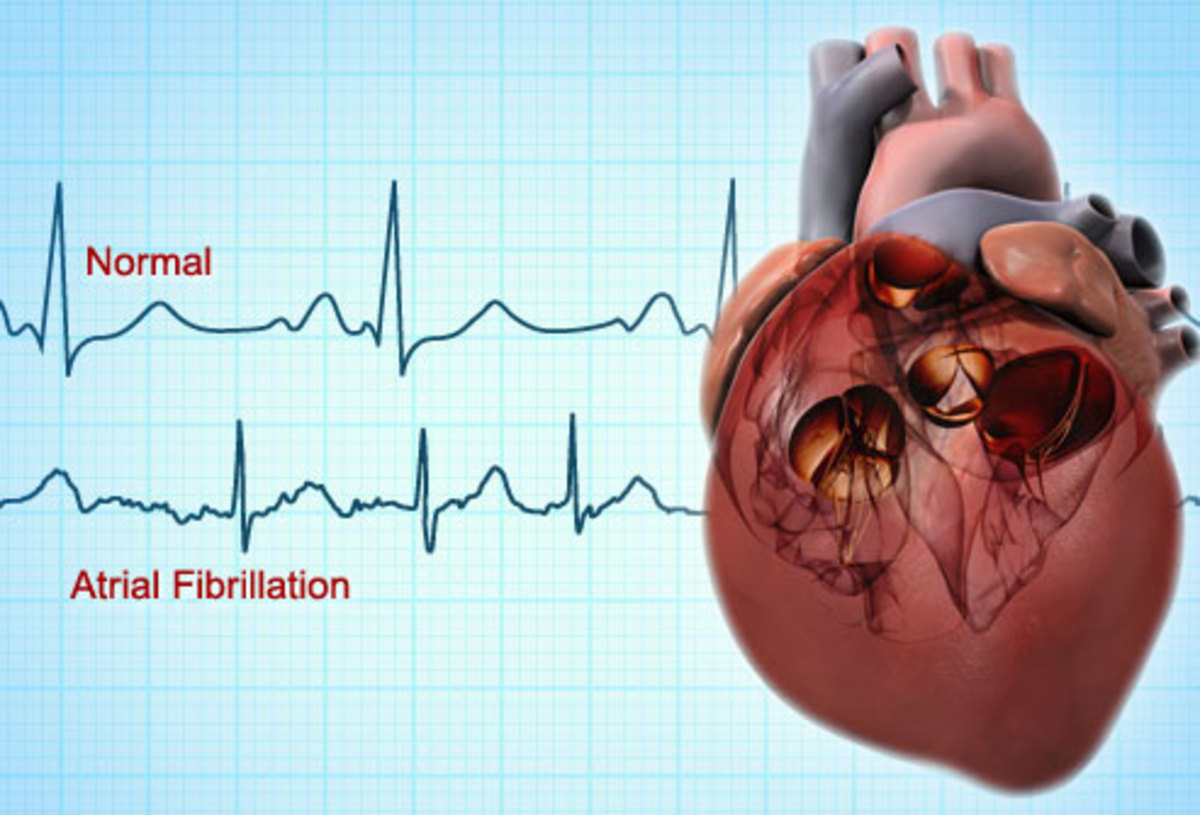

Στην κολπική μαρμαρυγή, ο καρδιακός ρυθμός μπορεί να φτάσει ακόμα και πάνω από 140 παλμούς το λεπτό. Η κύρια διαφορά μεταξύ ενός κανονικού ρυθμού και της κολπικής μαρμαρυγής είναι ότι δεν μπορείτε να προβλέψετε πότε θα είναι ο επόμενος καρδιακός παλμός. Αυτό συμβαίνει, επειδή υπάρχει ταυτόχρονα και αρρυθμία. Δηλαδή, κατά τη διάρκεια της κολπικής μαρμαρυγής, οι δύο άνω κοιλίες της καρδιάς χτυπούν ακανόνιστα και εκτός συγχρονισμού με τις δύο κάτω κοιλίες.

Ο φυσιολογικός καρδιακός ρυθμός ενός ατόμου θα πρέπει να είναι μεταξύ 60 και 100 παλμών το λεπτό όταν είναι σε κατάσταση ηρεμίας. Μπορείτε να μετρήσετε τον καρδιακό σας ρυθμό ψηλαφίζοντας τον καρπό ή το λαιμό σας.